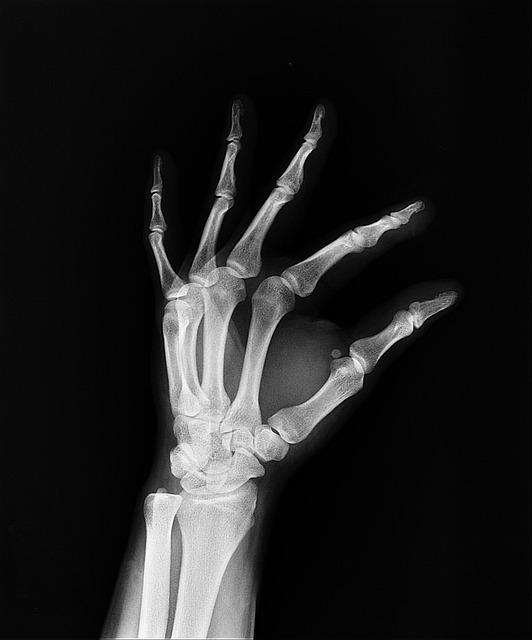

La proyección craneocaudal es una técnica radiográfica utilizada en el diagnóstico médico para obtener imágenes detalladas de las estructuras internas del cuerpo. En este proceso, se toman radiografías en las que los rayos X atraviesan el cuerpo de arriba abajo, proporcionando una vista frontal de las áreas a examinar.

Algunas de las aplicaciones más comunes de la proyección craneocaudal en el diagnóstico médico incluyen la detección de fracturas en los huesos, la evaluación de la posición de órganos internos y la detección de anomalías en las estructuras del cuerpo. Esta técnica es especialmente útil en el estudio de la columna vertebral, el tórax y el abdomen.

Algunas de las aplicaciones más comunes de la proyección craneocaudal incluyen la detección de fracturas, lesiones musculares, alteraciones en la columna vertebral, malformaciones congénitas y tumores. Gracias a esta técnica, los médicos pueden identificar de manera precisa y oportuna diversas condiciones médicas, lo que permite iniciar un tratamiento adecuado y mejorar el pronóstico de los pacientes.